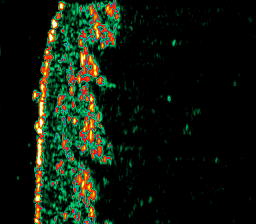

| Cellulite |  Cellulite 1, thigh |

Cellulite2, thigh |

Cellulite 3, thigh |